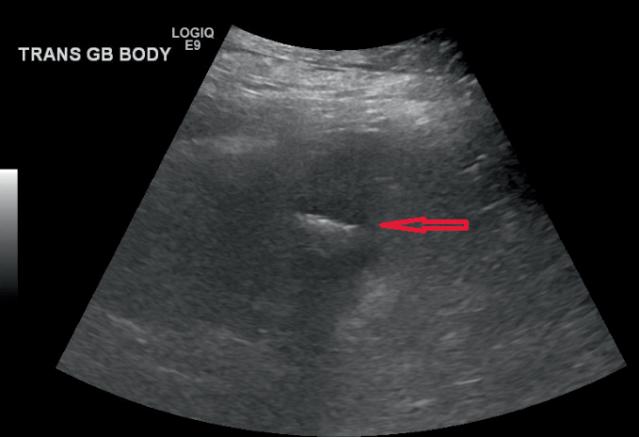

一名49岁的女性患者因上腹部疼痛伴恶性呕吐于当地医院急诊科就诊,两个月前患者因胆石症,胆总管扩张,梗阻性黄疸行内镜逆行行胰胆管造影术,,取出3块胆石,如图1、2。行腹部CT检查,提示小肠梗阻,胆石性肠梗阻,十二指肠瘘,如图3、4。患者立即行急诊手术治疗,术中发现扩张小肠有明显胆石阻塞及压迫痕迹,取出胆石,由于小肠压力过大,出现部分坏死,因此行小肠部分切除术,如图5。在距离回盲部60cm小肠处取出大小约3.5cm*3.5cm胆结石,如图3。用腹腔镜从Treitz韧带检查小肠,并未发现有残余结石,病人在手术后已康复,顺利出院。

图2 腹部超声提示胆囊结石